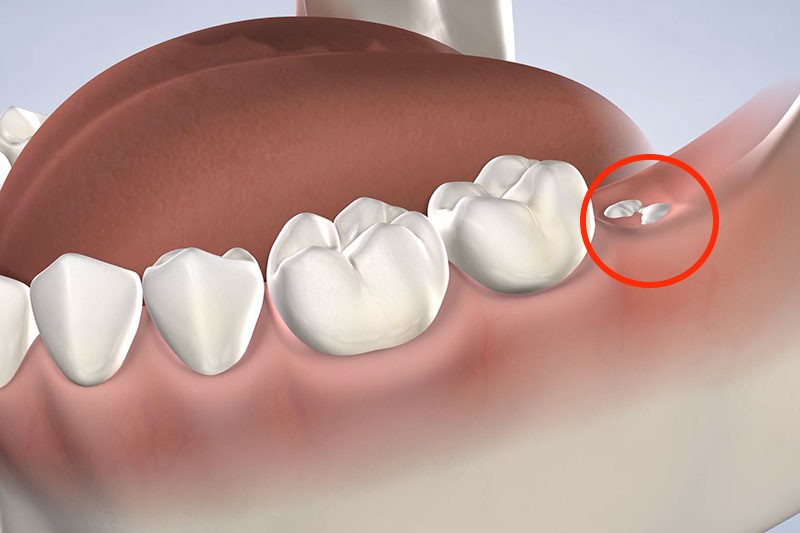

Vì mọc khi xương hàm đã cứng cáp, có niêm mạc, mô thì phủ dày bên trên nên khi răng khôn xuất hiện chúng sẽ thiếu không gian để phát triển. Cũng vì vậy mà những chiếc răng khôn thường mọc ngầm, bị lệch lạc hay đâm cả vào chiếc răng bên cạnh vì thiếu chỗ. Do đó quá trình mọc răng khôn khiến chúng ta bị đau đớn âm ỉ, khó chịu vô cùng. Những người bị nặng còn bị đau buốt, viêm nhiễm.